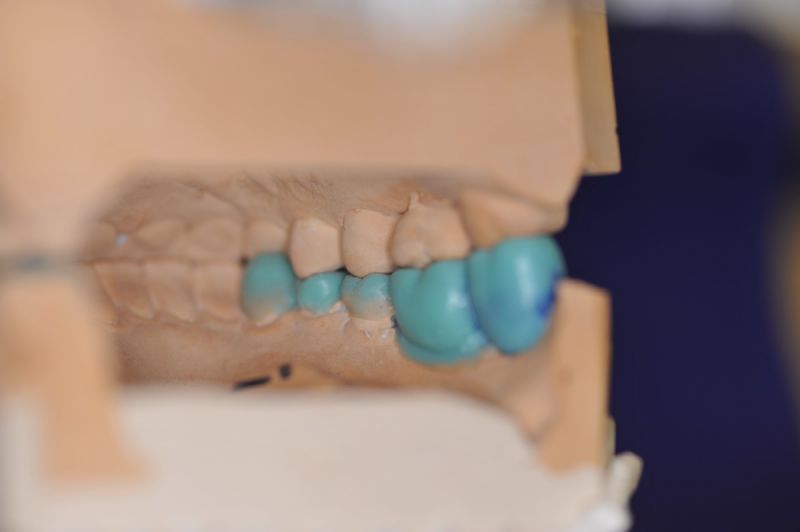

Es war eine Kombination aus Schmerzen bis an die Suizidgrenze, beschränkten wirtschaftlichen Möglichkeiten, sehr stark eingeschränkten Möglichkeiten der für Implantate zur Verfügung stehenden Knochenverhältnisse in einem stark atrophierten Unterkieferseitenzahnbereich und zudem dann auch noch durch auftretenden Problemen bei der Implantatinsertion und nachfolgenden Versorgung der Implantate.

Die Problematik der Implantatversorgungen kann man in einer Analogie folgendermaßen darstellen. Die räumlich beengten Zustände gleichen dem Tanz eines Paares auf einer Briefmarke, und der gleichzeitigen Schritt- und Fusshaltung, dass beim Tanzen die Schuhe geputzt werden können!